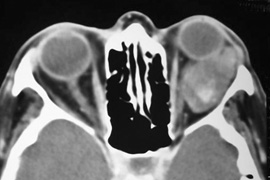

Valuable information about the nature and extent of an orbital pathologic process is provided by imaging studies such as computed tomography (CT) scan, magnetic resonance imaging (MRI), and orbital echography. Better spatial resolution, ready accessibility, and lower cost make CT the preferred choice for orbital imaging in most cases. Orbital fat provides a natural contrast between most adjacent orbital structures on CT scanning, and orbital bones are visualized well. Computed tomography is essential for evaluation of the orbital bones because they cannot be imaged with MRI. Direct coronal or sagittal images are important to identify the relationship of a lesion to the optic nerve so that the surgical approach can be planned to avoid traversing the optic nerve (Fig. 1).

Fig. 1. A. Axial CT scan demonstrating a large, well-encapsulated lesion in the orbital apex. Coronal (B) and sagittal (C) scans demonstrate that the mass lies inferior and medial to the optic nerve within the intraconal space. This information is useful in planning the surgical approach to the mass, which should avoid traversing the optic nerve.